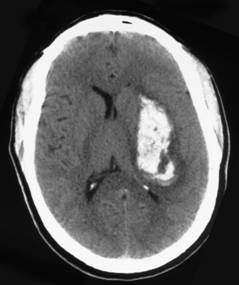

Scanner (sans injection) : HIP

capsulo-lenticulaire gauche chez un sujet hypertendu

diagnostic immdiat de lHIP : hyperdensit sanguine (restreinte au parenchyme crbral ou diffusant dans les mninges ou les ventricules).

scanner normal aux premières heures en cas dAIC, en dehors danomalies subtiles*. Au delà de la 6ème heure, hypodensit qui saccentue les premiers jours . Elle entraine, après plusieurs mois, une dilatation du ventricule en regard et à une atrophie localise du parenchyme.

LHTA est la principale cause dhmorragie intraparenchymateuse, de siège profond